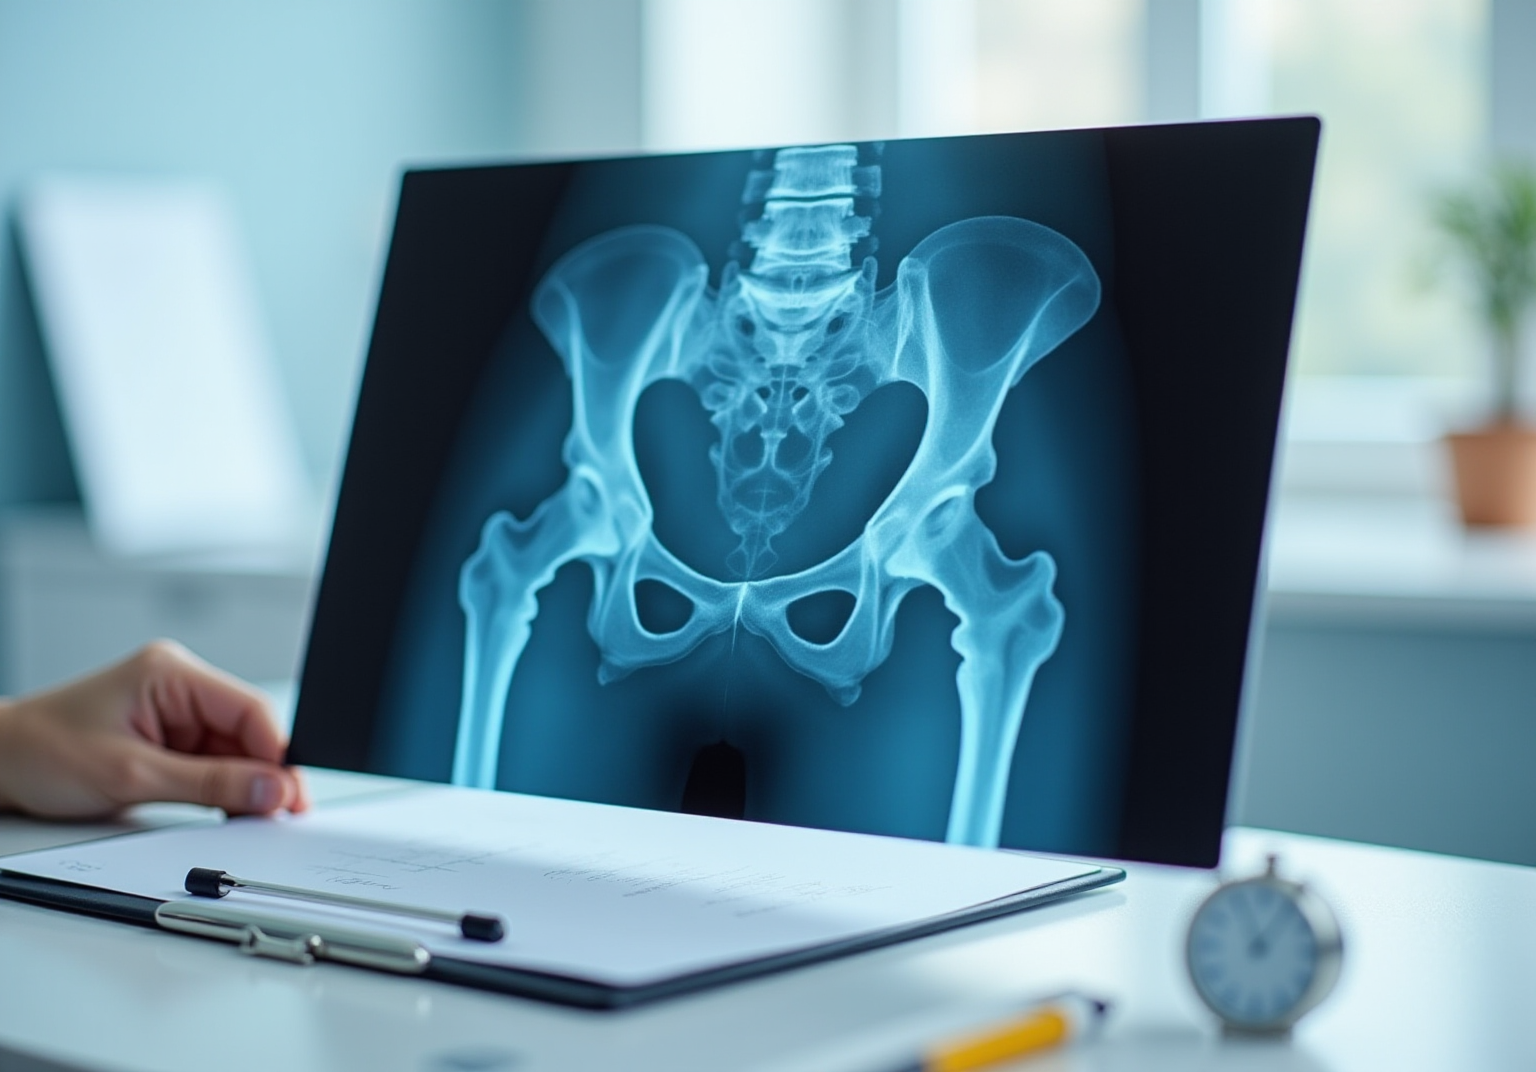

Explore the Role of X-Rays in Diagnosing Hip Osteoarthritis

For those grappling with hip osteoarthritis, the journey can often feel overwhelming, as seen in results. emerges as a vital ally in this battle, providing and the spaces between them. They reveal , such as joint space narrowing, the formation of bone spurs, and subchondral sclerosis. While X-rays alone can’t definitively diagnose OA, they are typically the used, thanks to their accessibility and speed.

Interpret Your Hip X-Ray: Step-by-Step Instructions

- Obtain the X-Ray: Start by ensuring you have the correct anteroposterior (AP) view of the hip. This standard view is crucial for , as it allows for a clear understanding of the involved. Having the right perspective is essential for making that can guide your next steps in care.

- Evaluate Articular Space: As you look at the X-ray, pay close attention to the space between the femoral head and the acetabulum. A can be a sign of cartilage loss, which is a significant indicator observed in an . Research indicates that when the space width (JSW) falls below 2 mm, it often points to , which can be confirmed by an . This finding underscores the seriousness of the disease and the need for .

- Identify Osteophytes: Next, check for osteophytes – those bony projections that can develop along the edges of the joints. Their presence often signals ongoing , a common challenge faced by many individuals living with osteoarthritis, which can be assessed through an . Recognizing these signs can help in understanding the patient’s journey and the impact on their daily life.

- Assess Subchondral Changes: Look for , which indicates increased bone density beneath the cartilage, and any cyst development. These changes may suggest that joint degeneration has progressed, highlighting the importance of a thorough assessment to ensure that the patient receives the attention they need.

- Document Findings: Finally, take the time to document your observations carefully. Note any significant changes or abnormalities that might require further investigation or intervention. Accurate documentation is not just a formality; it plays a vital role in ongoing patient management and care planning, ensuring that each patient feels supported and understood throughout their journey.